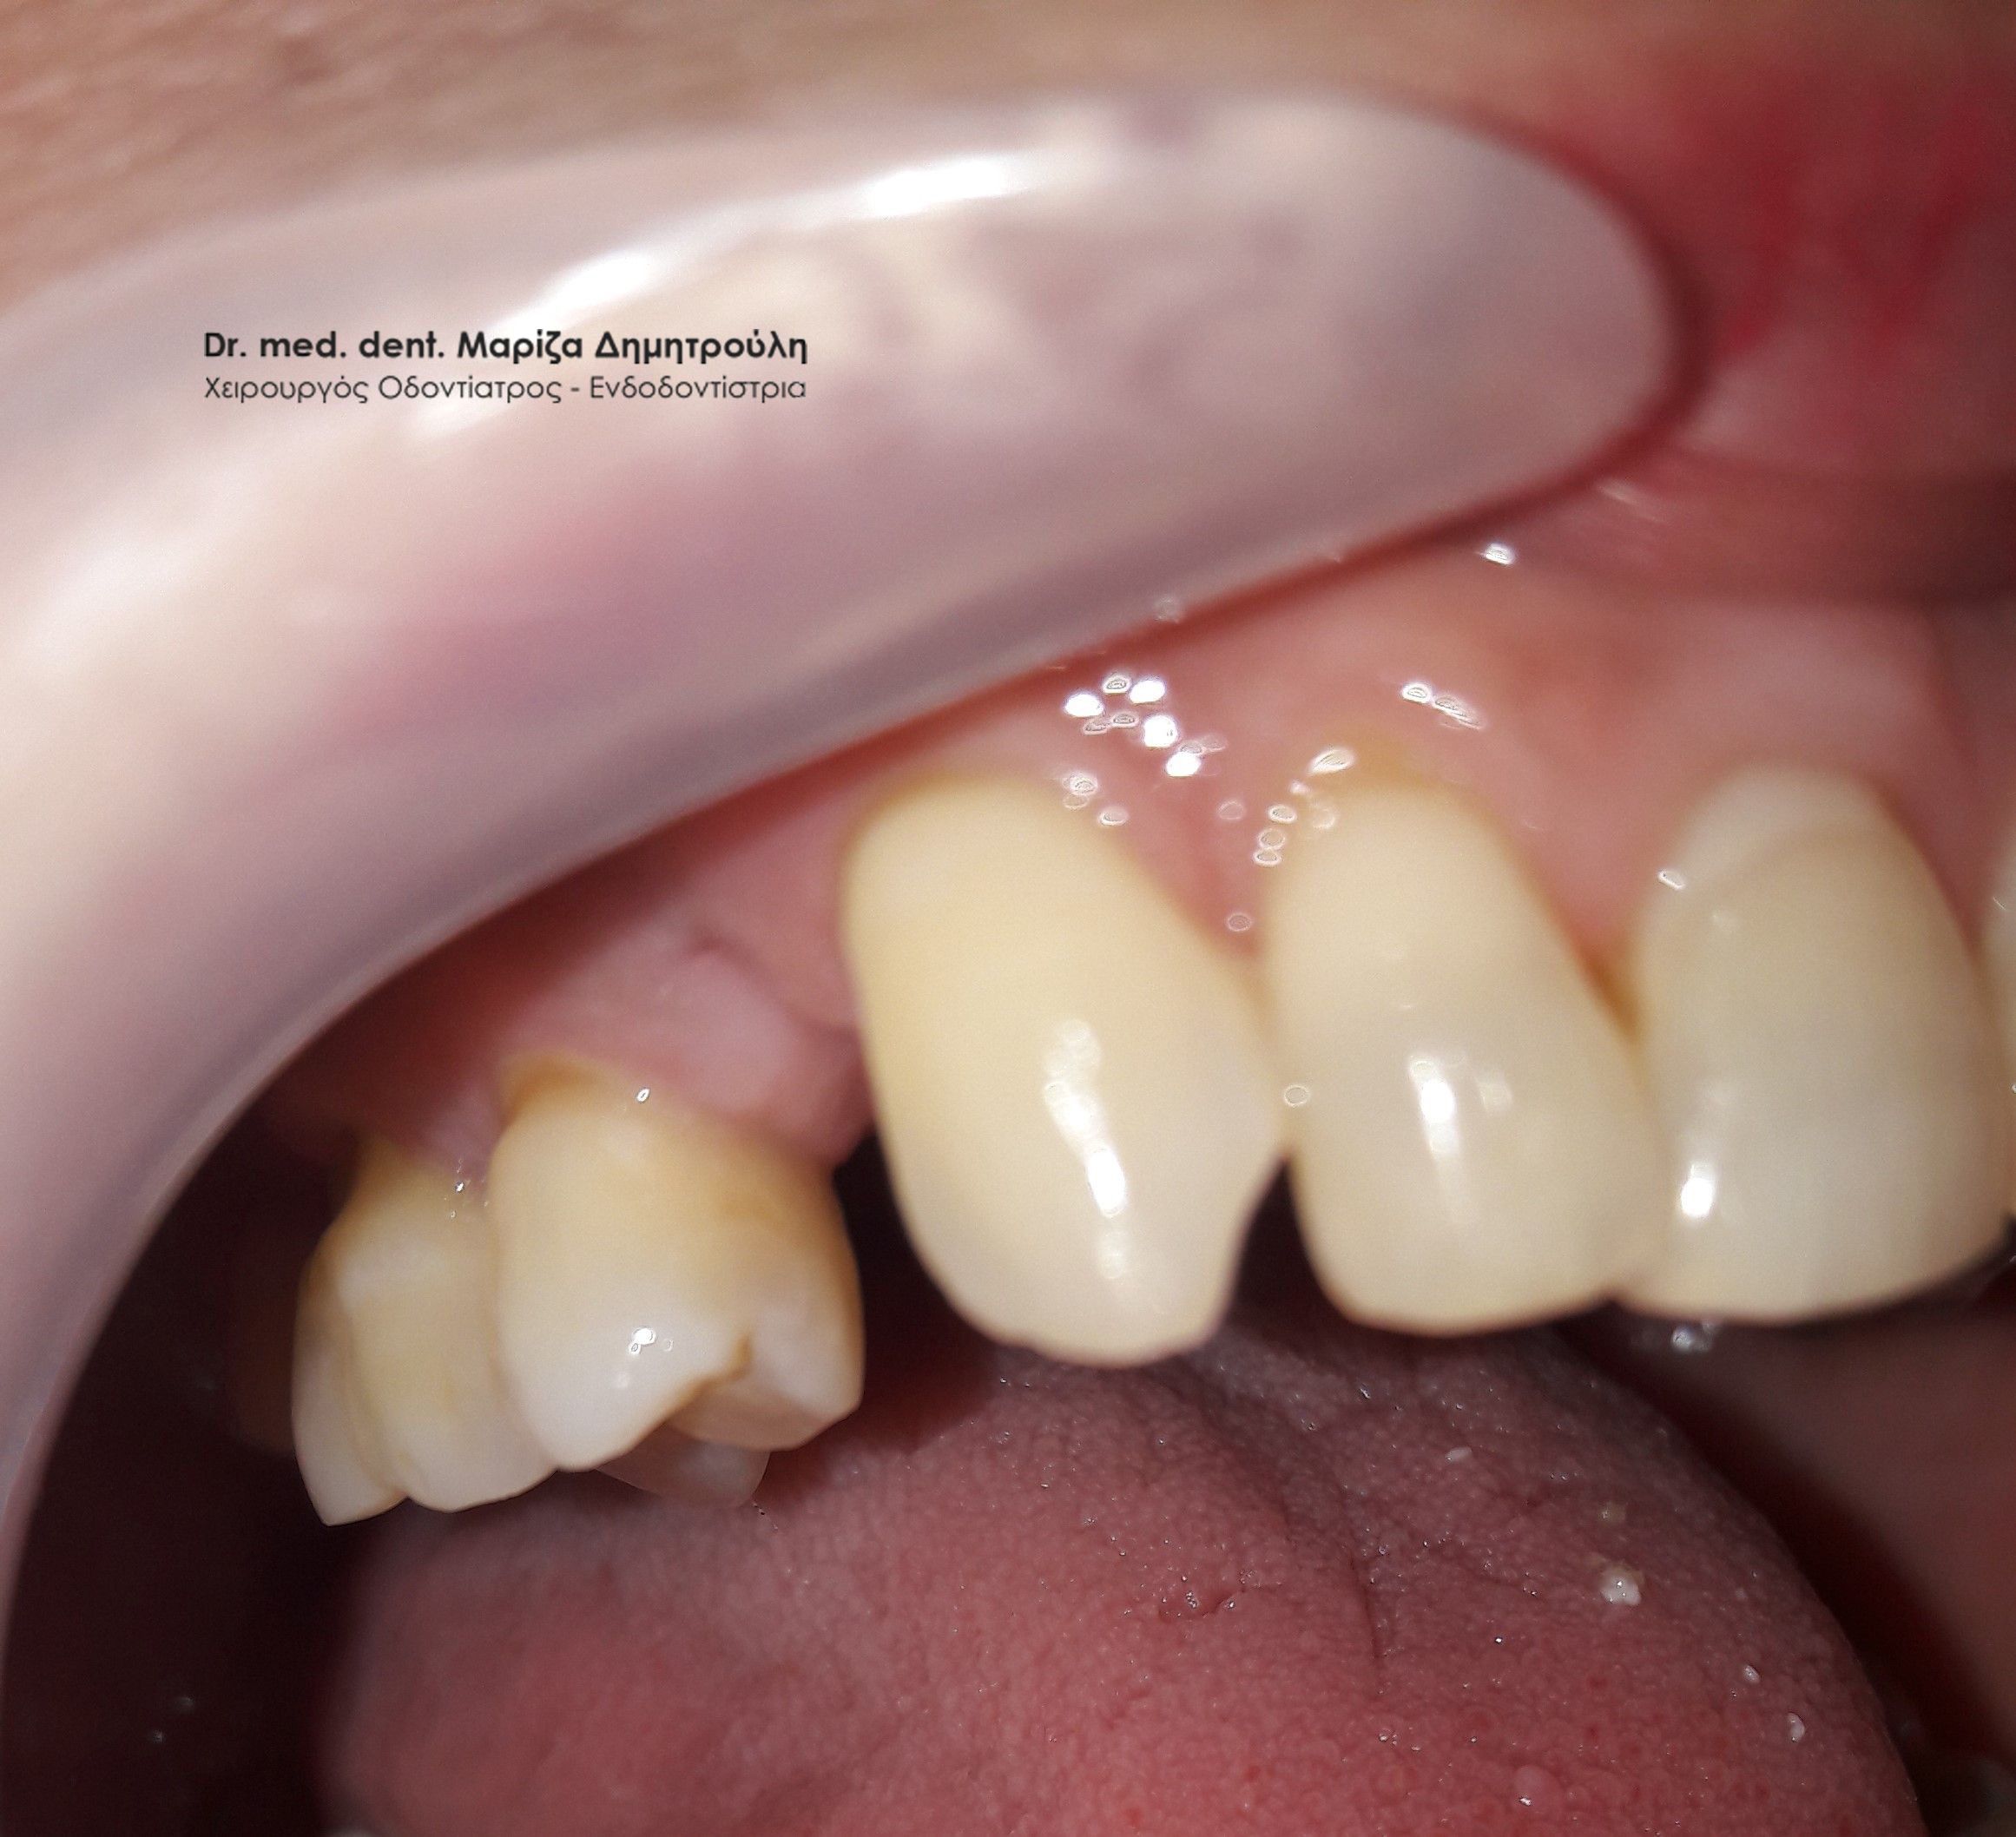

Περιστατικό – Ολοκεραμική στεφάνη / θήκη ζιρκονίου στον άνω αριστερό γομφίο

Η ασθενής επισκέφτηκε το ιατρείο μας γιατί πονούσε στον πρώτο άνω αριστερό γομφίο. Η κλινική και ακτινογραφική εξέταση φανέρωσε την αναγκαιότητα απονεύρωσης του δοντιού. Μετά το πέρας της ενδοδοντικής θεραπείας και εφόσον το οδοντικό έλλειμα ήταν μεγάλο, κρίθηκε απαραίτητη η προστασία του απονευρωμένου δοντιού με ολοκεραμική θήκη.

Τελική κλινική εικόνα με την ολοκεραμική θήκη δοντιού